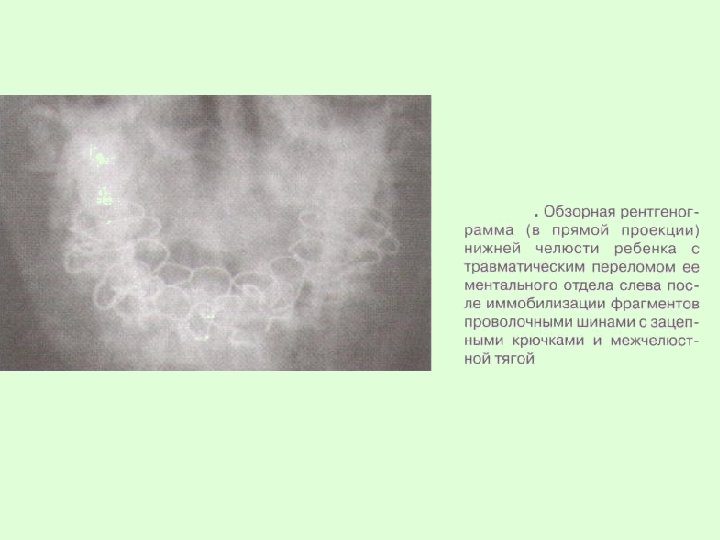

Заключительный диагноз перелома нижней челюсти ставят после проведения рентгенологического исследования в боковой укладке по Генишу или обзорной рентгенограммы нижней челюсти в прямой проекции, при переломе суставного отростка – ортопантомограммы или рентгенограммы сустава по Шуллеру или Парма.

Для обеспечения покоя нижней челюсти после репозиции отломков применяются проволочные шины с зацепными петлями и межчелюстной тягой (у детей старшего возраста) или шины-каппы (у детей младшего возраста).